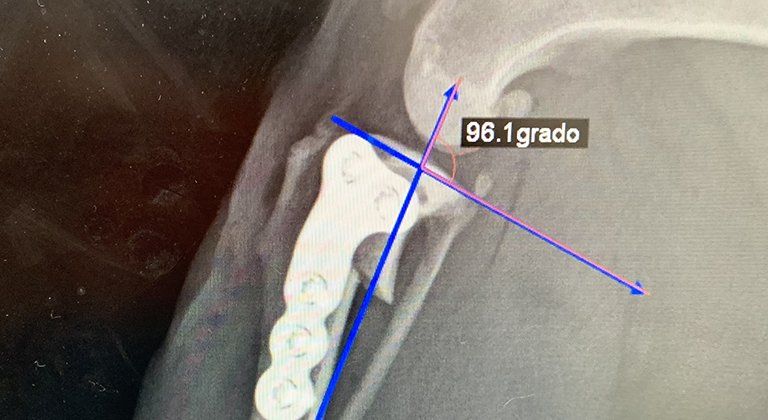

Ortopedia

Presso la Clinica possiamo eseguire una grande varietà di interventi: quelli considerati routinari, ma che richiedono comunque attenzione e professionalità, come la sterilizzazione di cani e gatti. Ma anche interventi complessi che attengono a diverse branche: quelli di ortopedia su arti e bacino (TPLO, TTA, DPO), interventi di oftalmologia su palpebra e cornea, interventi in endoscopia e chirurgia dedicata agli animali non convenzionali.